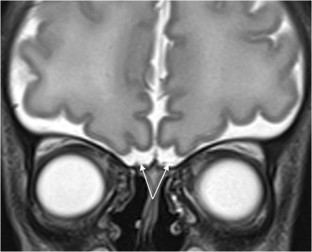

We selected pediatric head MRI examinations from 2005 to 2017 based on the finding of a double midline sellar and suprasellar bright spot on T1-weighted sequence. Medical history, physical examination, pituitary hormonal profile and bone age evaluation were extracted from the medical record of the selected patients. An experienced pediatric neuroradiologist reviewed head MRIs, which were performed on 3-tesla (T) magnet and included at least sagittal T1-weighted imaging centered on the sella turcica obtained with and without fat suppression.

In six cases, two midline bright spots were identified on T1-weighted sequences obtained both with and without fat suppression. While one spot was located at the expected site of the neurohypophysis in the posterior sella, the second one was in the region of the median eminence, suggesting partial ectopic posterior pituitary gland. Growth hormone deficiency, either isolated (n=1) or combined with thyroid stimulating hormone deficiency (n=1) was found. None of the children had clinical signs of posterior pituitary dysfunction.